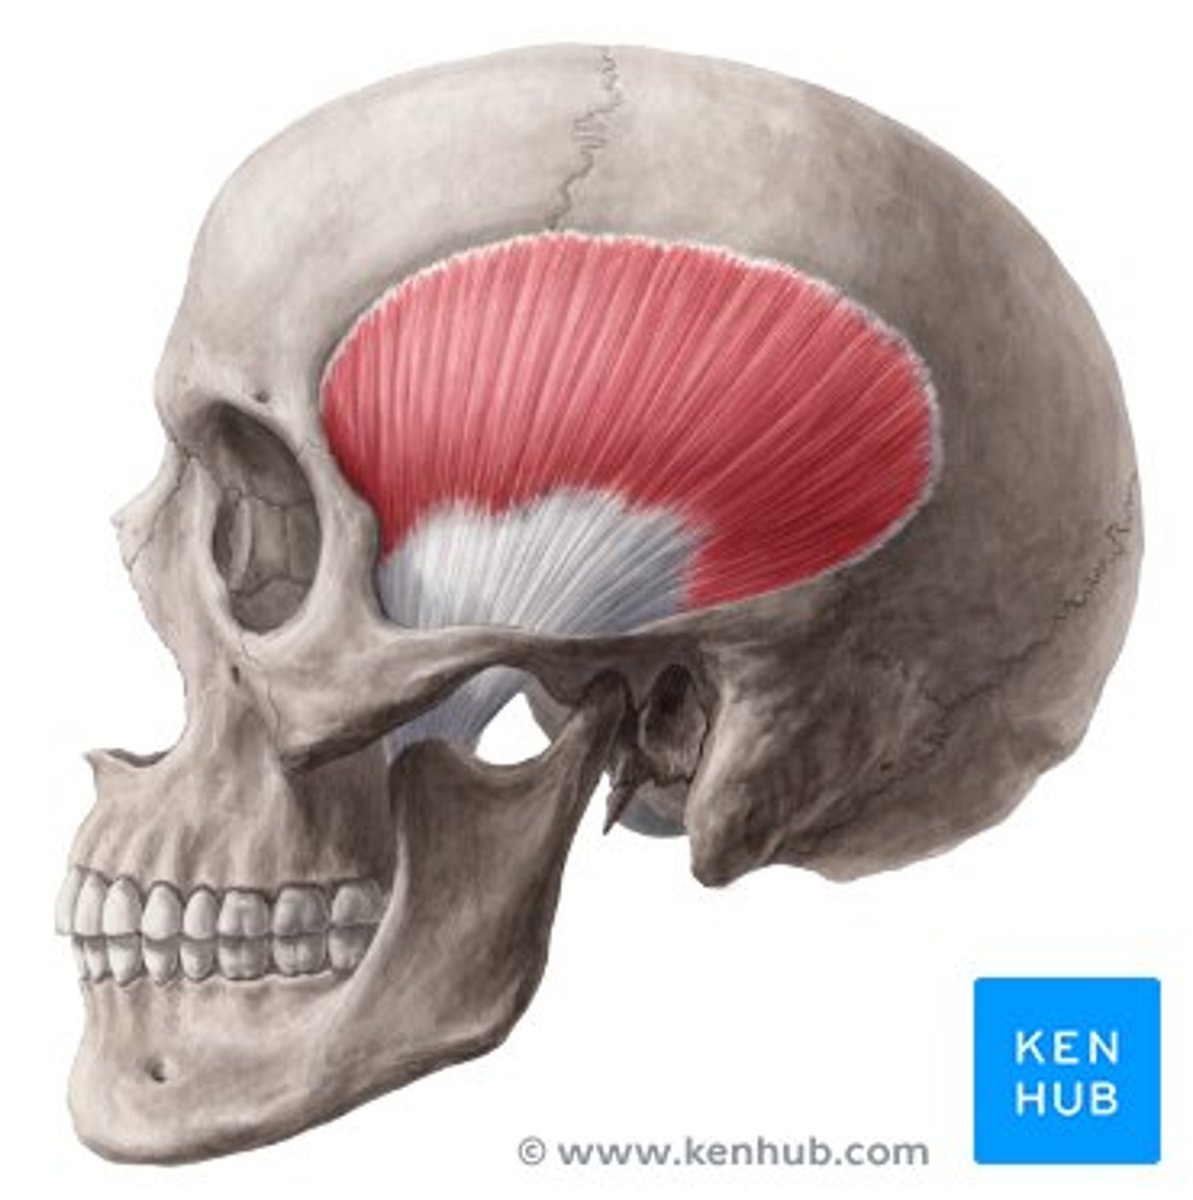

temporalis